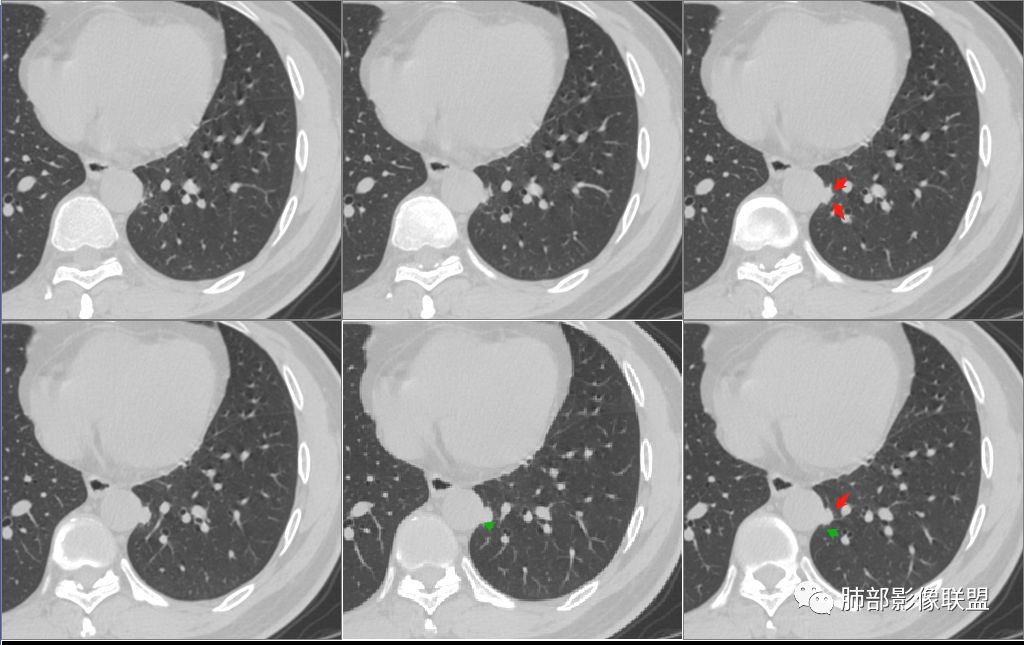

病例一:右肺下叶胸膜下结节,边缘毛糙,可见长短不一毛刺,形态欠规则,周围血管增粗牵拉,近段支气管壁略增厚,远端胸膜局限性增厚,并牵拉胸膜,平扫密度尚均匀,增强后明显强化(强化增加30Hu),考虑炎性肉芽肿:(隐球菌,炎性假瘤)鉴别:腺癌

病例1男,49,右肺下叶见实性结节影,边缘呈磨玻璃样改变,可见长短不一毛刺,分叶及胸膜牵拉,相应层面胸膜局限性增厚,增强扫描,病灶内见坏死,考虑腺癌可能。

病例一:右肺下叶胸膜下结节,边缘可见长短不一毛刺,形态欠规则,周围血管增粗牵拉,近段支气管壁略增厚,远端胸膜局限性增厚,并牵拉胸膜,腺癌? 医学百科网 | YxBaike.Com

1:右肺下叶胸膜下实性结节,可见长短不一毛刺,周围血管增粗,胸膜增厚,增强后强化,腺癌? 医学百科网 | YxBaike.Com

1.右肺下叶密度不均匀结节,边缘浅分叶,周围短毛刺及磨玻璃影,内见小空泡征,胸膜牵拉明显并局部胸膜增厚;增强扫描CT值增加小于60HU,考虑腺癌可能。

2.左肺下叶内基底段旁实性小结节,密度尚均匀,边境尚光整,增强扫描明显强化,多考虑炎性结节,主动脉周围可见弧形低密度充盈缺损,若一元论考虑的话需鉴别大动脉炎。

病例一:右肺下叶胸膜下实性结节,边缘毛糙,可见长短不一毛刺,形态欠规则,部分平直,部分膨隆,周围血管增粗牵拉,近段支气管壁略增厚有阻塞,远端胸膜局限性增厚,并牵拉胸膜,周围磨玻璃影,边缘模糊,平扫密度尚均匀,增强后明显强化(强化增加30Hu),其内有坏死区,分界不清,实性结节,收缩力太强了,所以首先考虑炎性肉芽肿:(隐球菌,炎性假瘤)鉴别腺癌; 医学百科网 | YxBaike.Com

病例二:主动脉旁实性结节,平扫密度均匀,增强后均匀强化,与主动脉壁分界清楚,可惜只有一层,考虑:良性结节,鉴别主动脉周围炎

病例一:右肺下叶胸膜下结节,边缘长软毛刺,周围血管增粗牵拉,胸膜牵拉增厚,胸膜增厚范围比较广,增强后明显强化,中央可见低密度坏死,考虑炎性肉芽肿:结核,隐球菌。鉴别:腺癌。

病例二:主动脉壁增厚,可见向壁外凸起结节,增强后明显强化,强化值117,考虑:主动脉溃疡,假性动脉瘤

病例一之于肺腺癌无论如何都是难以排除的诊断,收缩能力如此之强!回顾性分析不支持腺癌的地方在于:1.结节缺乏典型深分叶;2如此大实性密度结节周围有磨玻璃晕,还是非常模糊的;3.结节邻近脏层胸膜的胼胝样增厚,居然还有强化,提示不是液体;4.(拉不直)的纤维长条索多是炎性的特点;5.腺癌除了自身脏层胸膜的收缩形成一个喇叭口样的凹陷以外很少与壁层胸膜粘连。通俗的讲腺癌的胸膜凹陷就像扎口袋往紧的收,而炎性只是像一枚印章敲在壁胸膜上。

病例二的特点同样符合马老师所讲的炎性特点。胸膜下实性小结节,有棘突提示来自肺组织。缺乏磨玻璃及分叶等周边征象,容易怀疑炎性病灶或肉芽肿,很难做出隐球菌感染的判断。